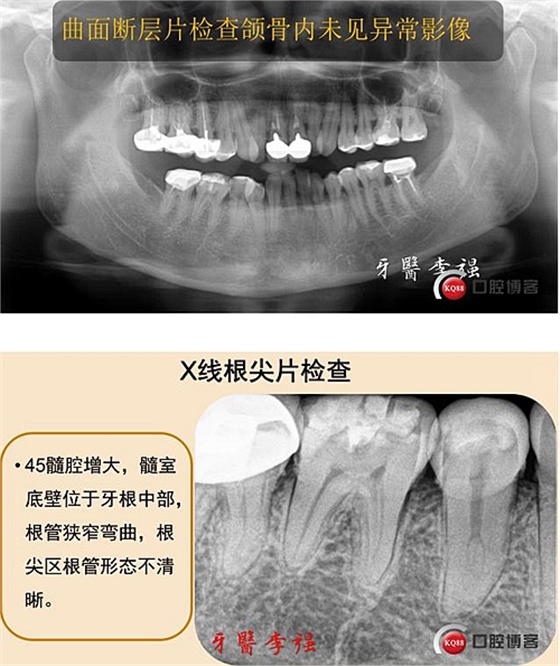

首頁(yè)牙體牙髓 第二前磨牙重度牛牙癥伴C型根管病例 科貿(mào)嘉友收錄

第二前磨牙重度牛牙癥伴C型根管病例 科貿(mào)嘉友收錄